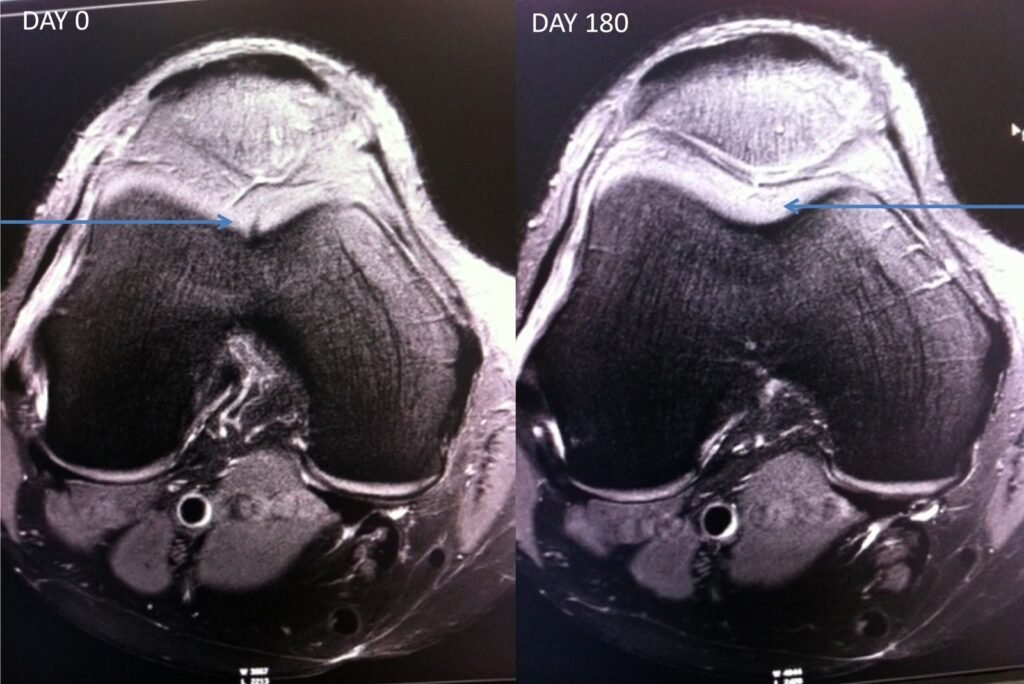

Results

Osteochondral defect – MRI Pre and Post

- 50 year male, Osteochondral defect due to impact

- Single application of GFC